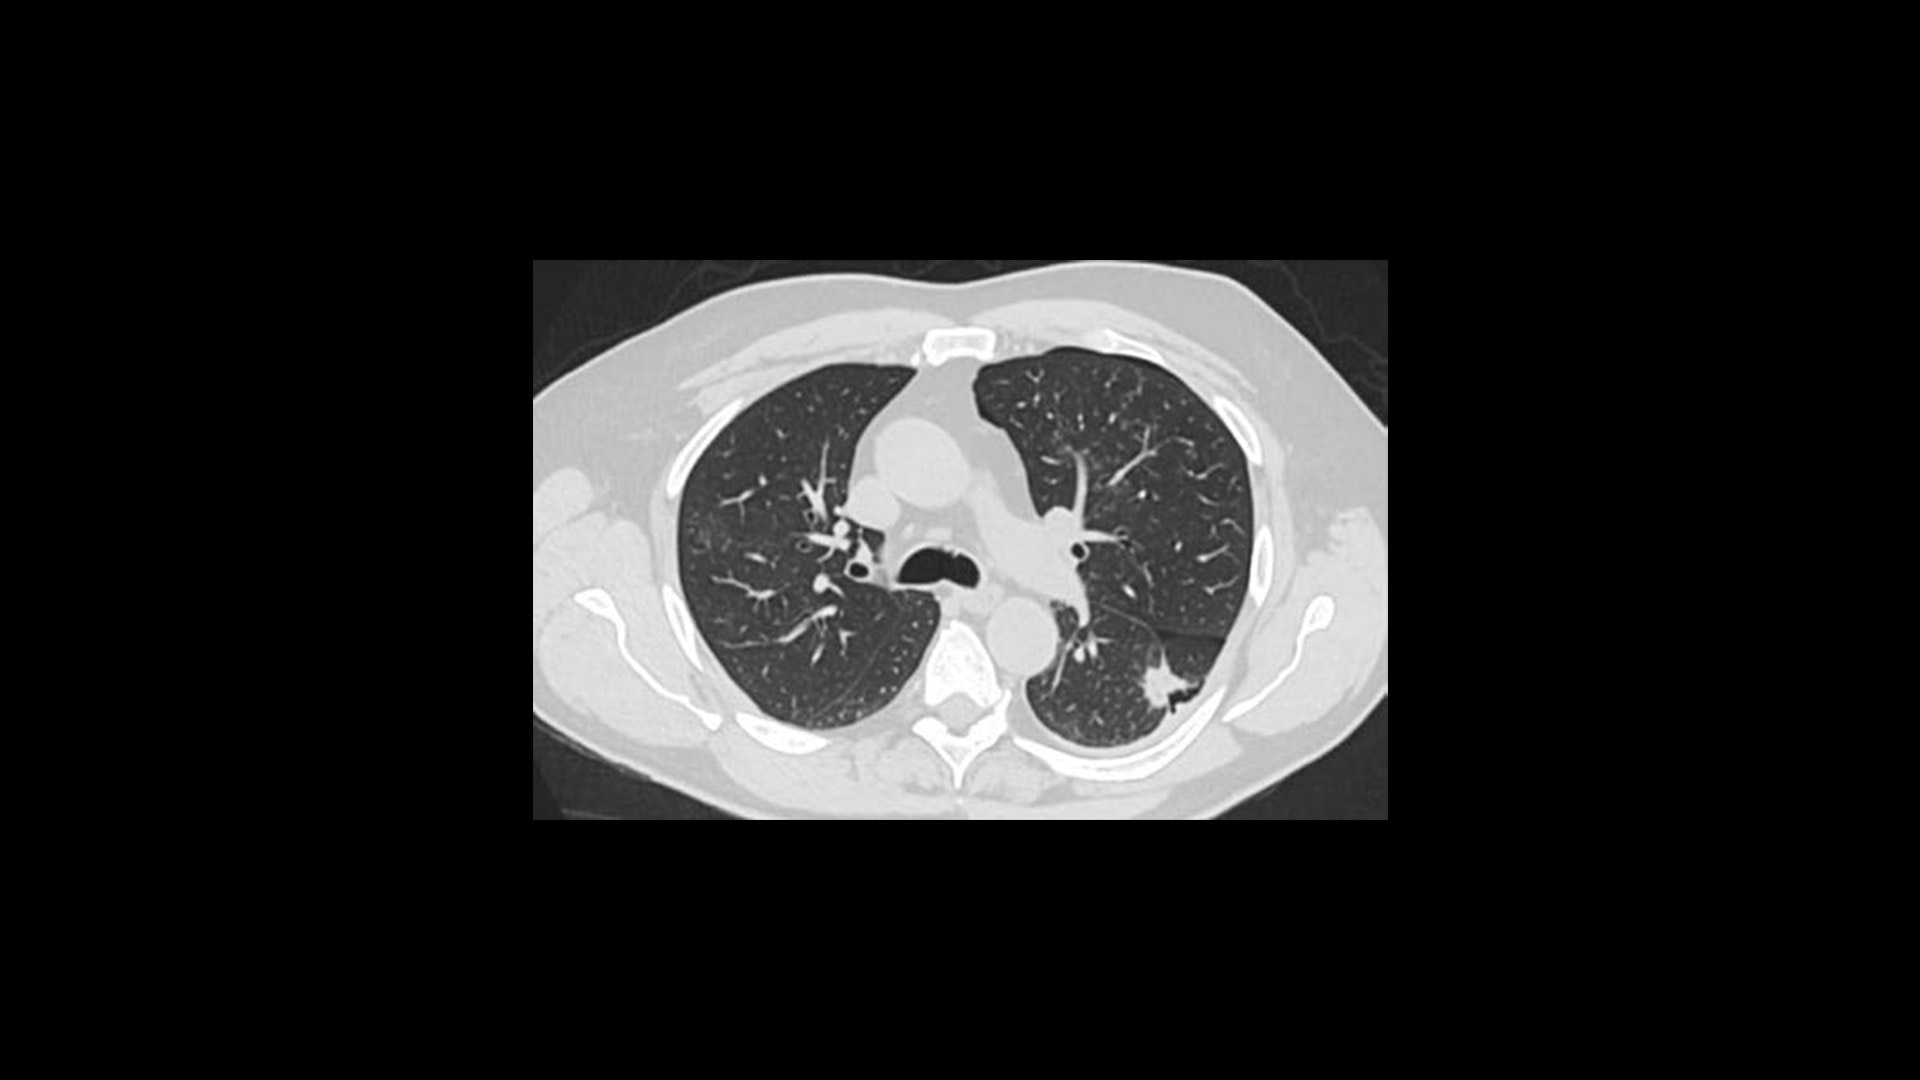

Effortless Workflow

Simplified scanning from start to finish

Available on all Revolution Ascend Platform configurations, Effortless Workflow intelligently automates your CT workflow from pre-scan protocoling to post-scan processing. It uses AI-based features to help transform the entire CT experience and provides maximum efficiency, accuracy, clarity and consistency.

This enables technologists to automatically and accurately personalize scans for each patient with significantly less effort. The end result is a beautiful CT image acquired in less time.